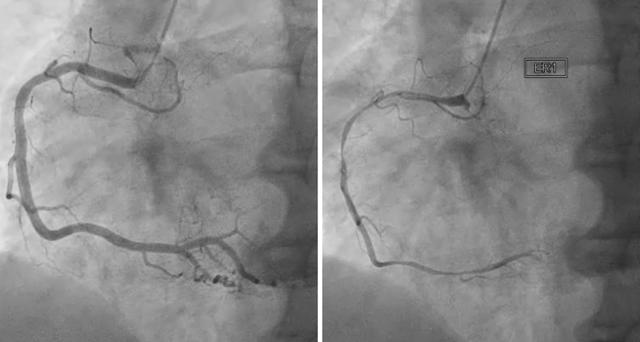

심장성형술과 스텐트 시술은 요골동맥이나 대퇴동맥을 통해 혈관이 막히거나 좁아진 곳을 찾아 혈관 조영술을 시행한 후 풍선과 스텐트라는 철망을 이용해 혈관에 카테터를 삽입해 혈관을 넓혀주는 시술이다. 대부분의 병원에서 일주일 이내에 또는 빠르면 다음 날 퇴원할 수 있습니다.